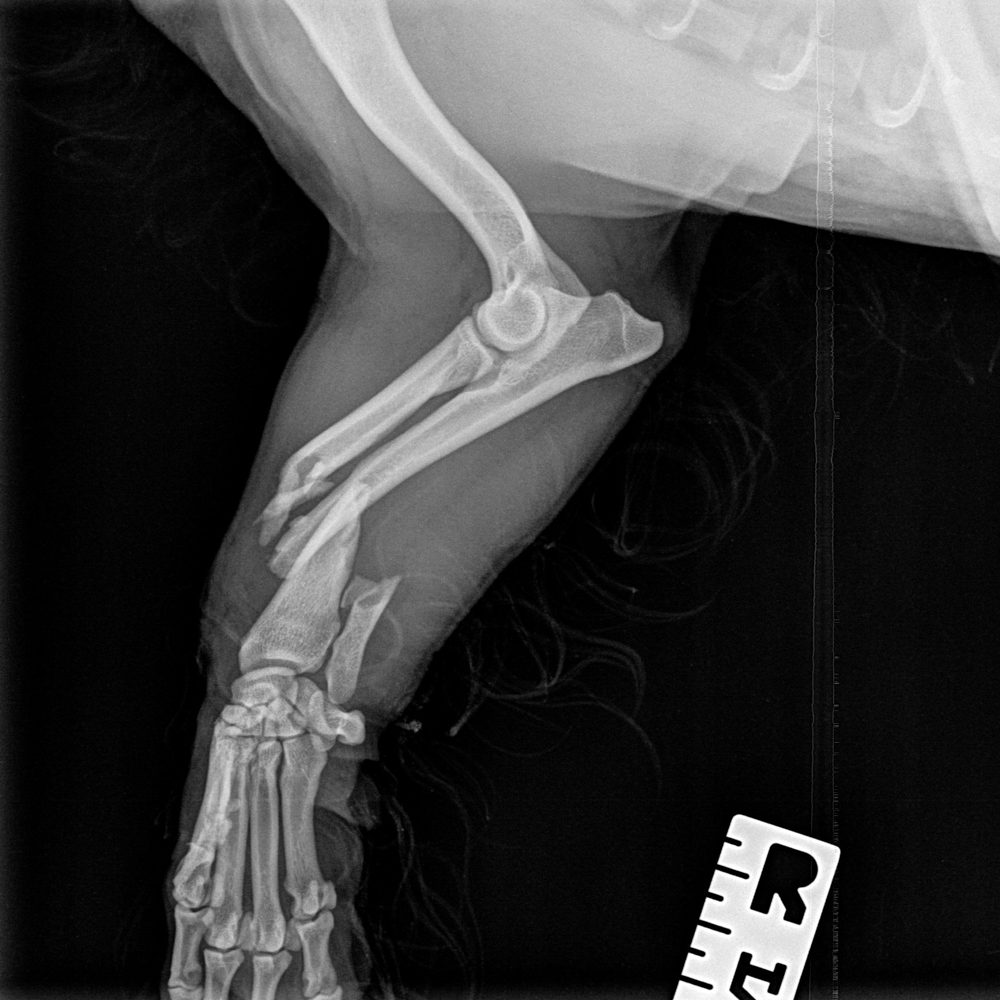

Fracture Repair

Many fractures can be managed by either internal (plate/ rod) fixation or external fixation (ESF). An estimate can be provided after review of radiographs, please include a size calibrated marker on films.